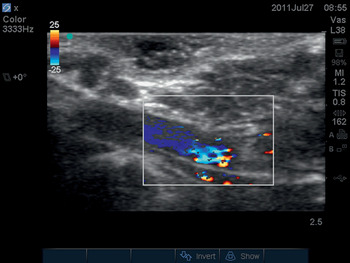

A transverse plane scan of the tissue volume beneath the planned site of skin incision should also be performed. The sonographer should inspect both the longitudinal and transverse scan images, looking for the presence of major blood vessels. In both planes, a 2D scan should be performed first. Blood vessels appear as a homogenous black area on a 2D scan. The operator can confirm the presence of a blood vessel by switching on the color Doppler ultrasound function (Figure 6.3*).